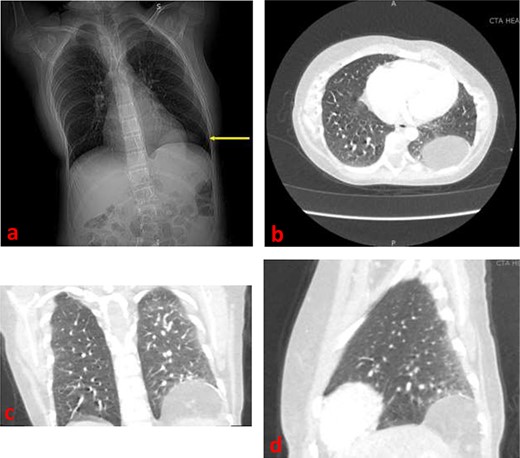

In the setting of the patient’s new symptoms and her history, a chest radiograph (Fig. 1a) and computed tomography (CT) scan (Fig. 1b–d) were ordered to fully characterize the state of the diaphragmatic hernia. Imaging revealed a 6 × 6 cm protrusion of retroperitoneal fat into the left posterior hemithorax. Given the increased growth in size of the defect that was becoming symptomatic, we performed a video-assisted thoracoscopic repair of the diaphragmatic hernia.

(a) Frontal chest radiograph demonstrating a left diaphragmatic hernia (arrow) (b) Axial contrast-enhanced CT image demonstrating a left diaphragmatic hernia in the left hemithorax (c) Frontal contrast-enhanced CT image demonstrating a left diaphragmatic hernia in the left hemithorax (d) Sagittal contrast-enhanced CT image demonstrating a left diaphragmatic hernia.